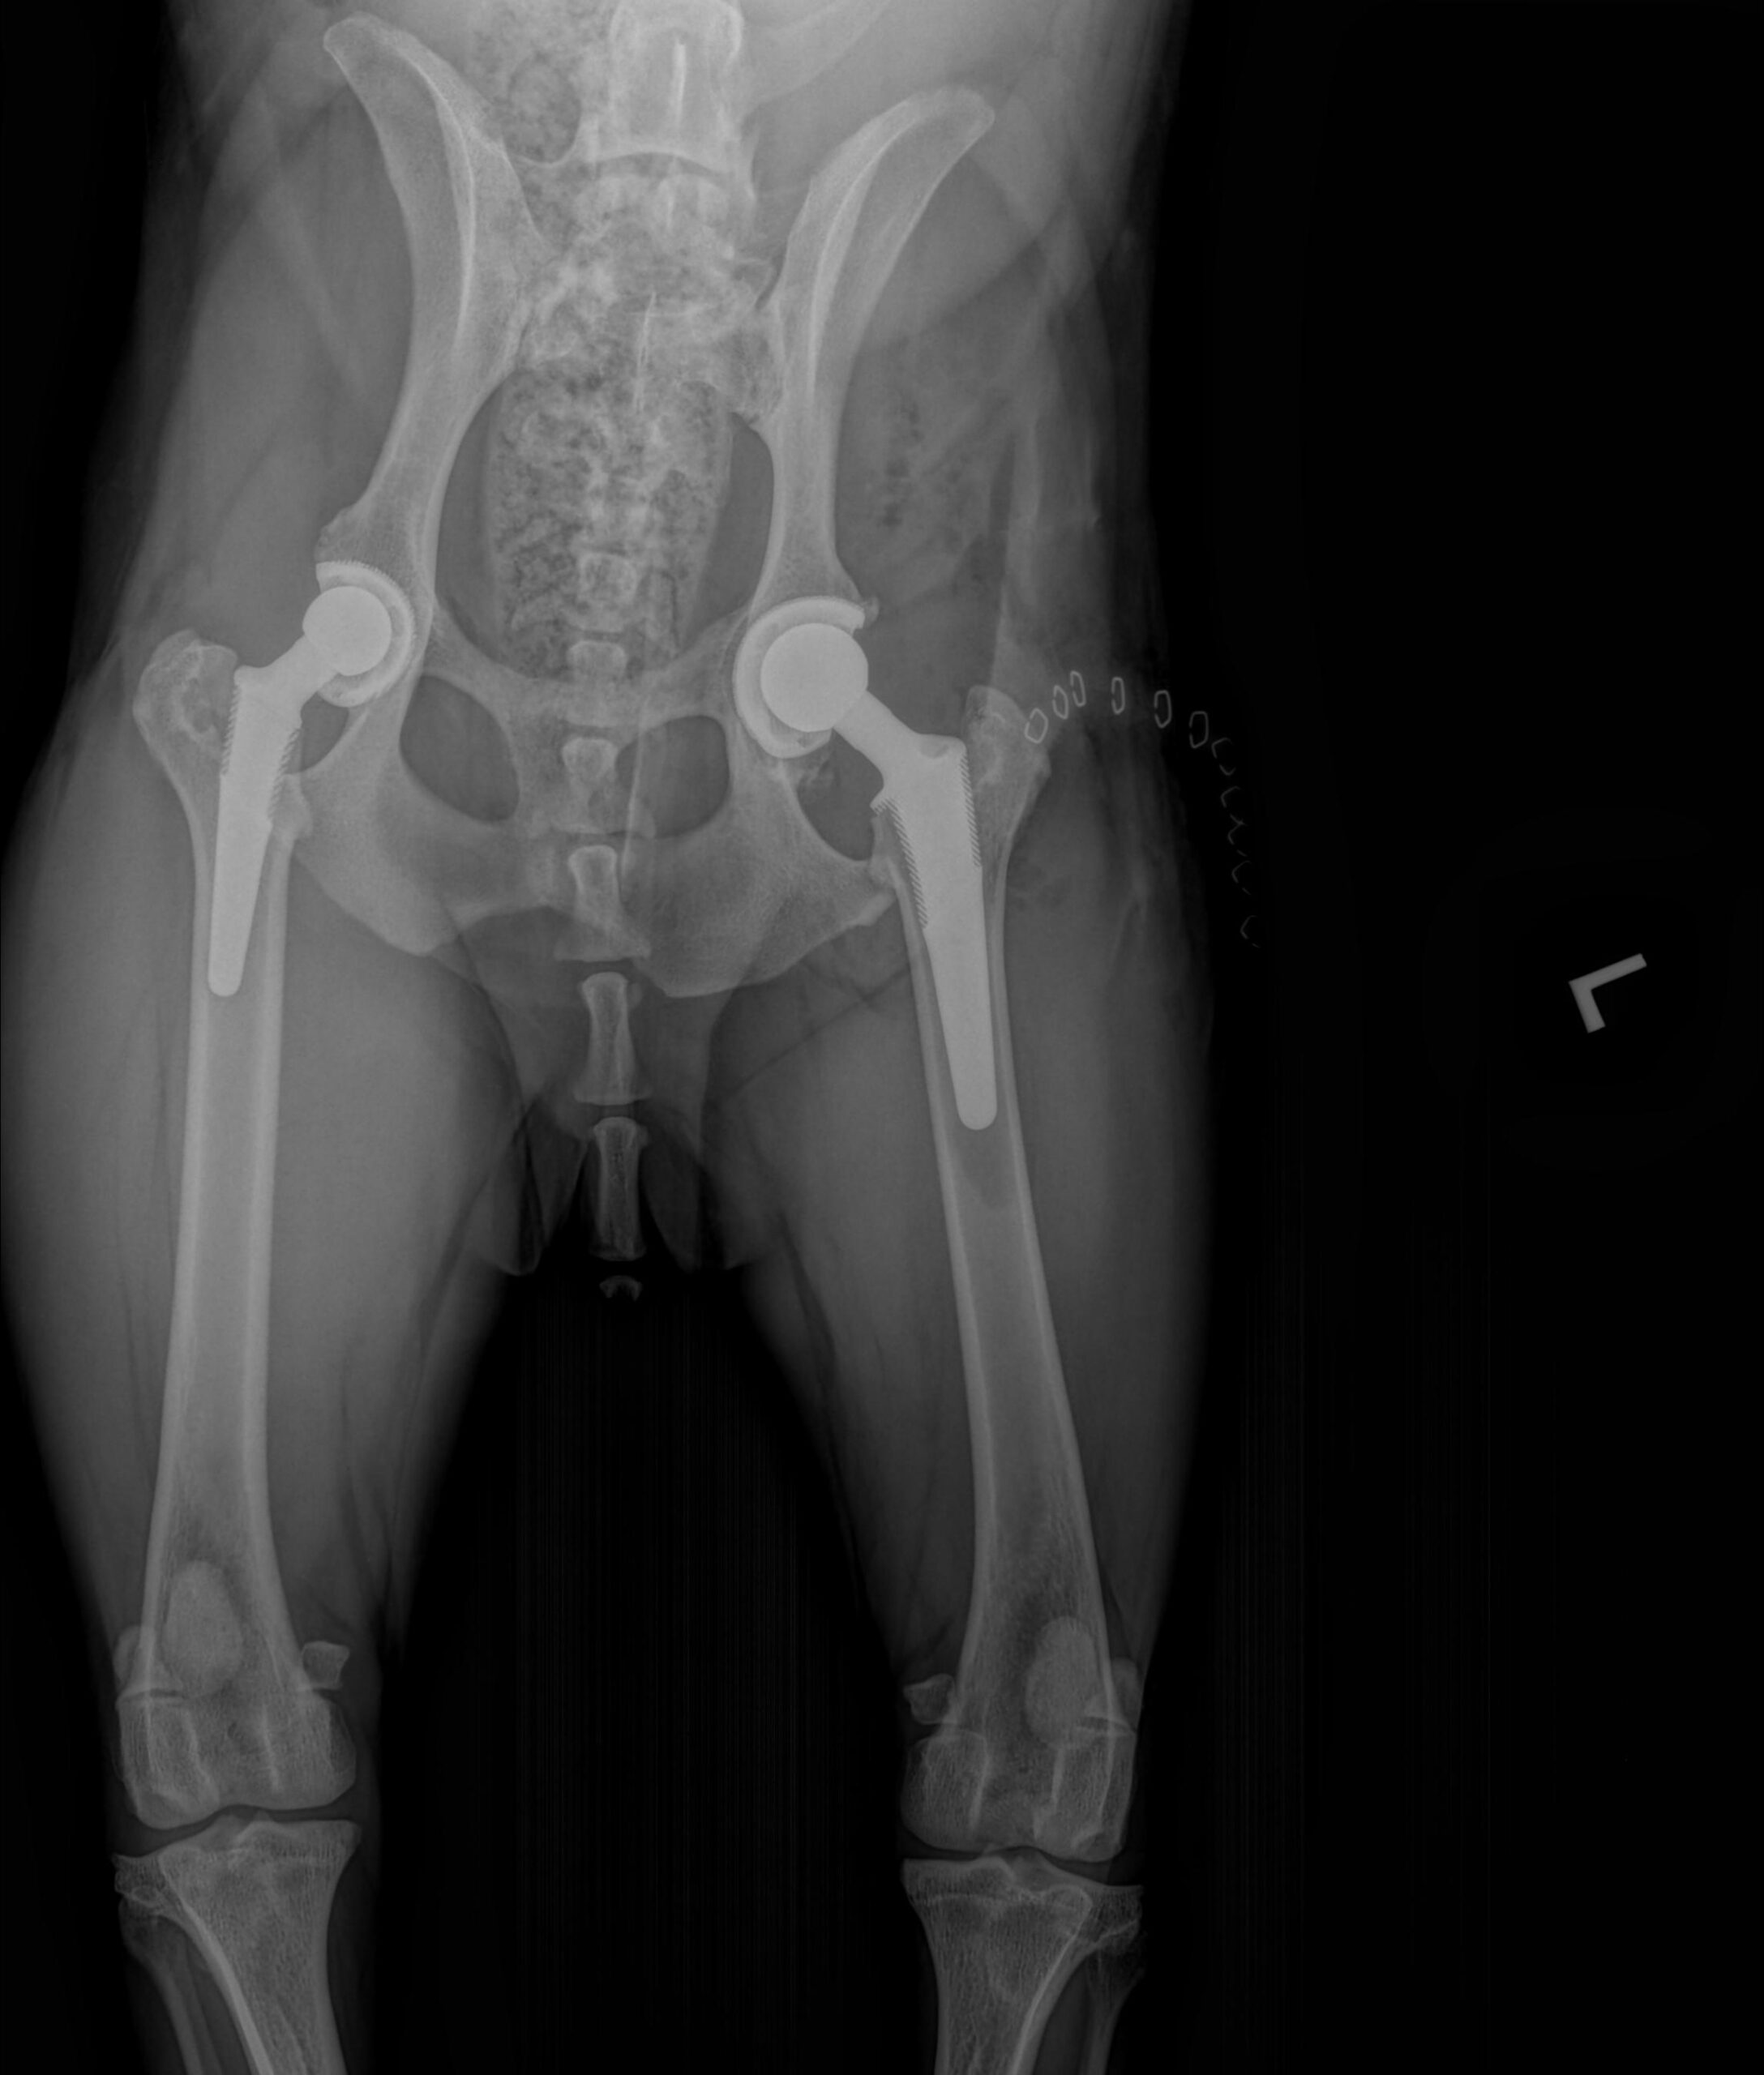

Treating hip dysplasia depends on the individual patient. Generally, treatment is divided into conservative (non-surgical) and surgical options. Conservative options focus on lifelong management strategies to improve hip extension, maintain muscle mass, and reduce pain. Weight control through a daily exercise plan and diet is essential. In addition, we may prescribe a program of physical rehabilitation. When surgery is indicated, the specific procedure we recommend generally relates to your dog’s age as well as their clinical symptoms:

If staples/sutures are present, they’ll be removed, or the incision evaluated, about 2 weeks after surgery. X-rays will be done at 4-6 and 8-10 weeks after surgery. At these rechecks, an orthopedic exam will also be performed to ensure everything is healing as expected.